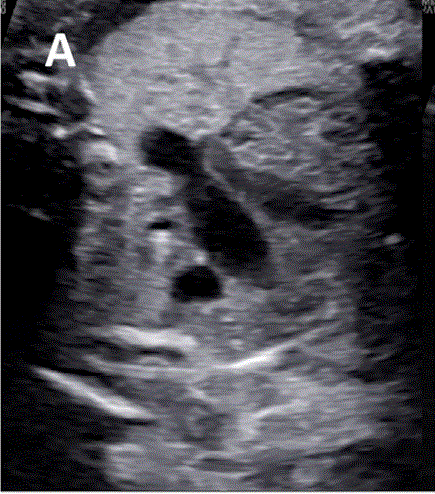

• 同侧大动脉弓的逆流预示着任何妊娠年龄 的半月瓣严重狭窄,如果在初次评估时未出现逆流,则应在妊娠期反复随诊(图 28)。

图28半月瓣狭窄同侧弓的逆流。(上图)严重右心室流出道梗阻,其中3VT看起来有些正常,但彩色多普勒显示动脉导管逆行(蓝色)。(下图)主动脉弓的矢状在2D图像上看起来正常,但彩色多普勒成像显示导管弓的逆(蓝色)流。